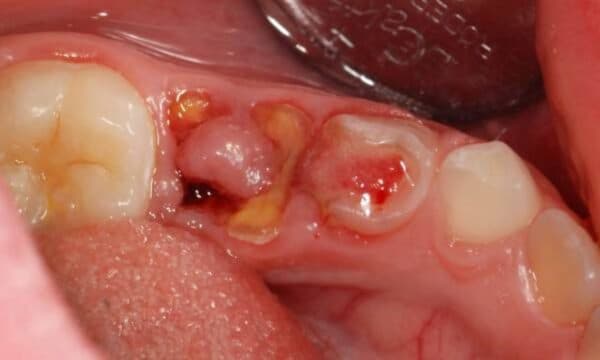

Sâu răng bị lồi thịt là hệ quả của răng sâu lâu ngày không được điều trị

Răng sâu bị lồi thịt là tình trạng có thể xảy ra với bệnh nhân bị sâu răng lâu ngày nhưng không được tiến hành điều trị. Theo thời gian, ổ viêm nhiễm sẽ lan rộng, tấn công vào răng và nướu.

Phần nướu đã bị vi khuẩn tấn công sẽ thối rữa, hoại tử và hình thành nên lỗ dò. Phần niêm mạc ở quanh lỗ dò cũng sẽ bị viêm nhiễm nặng, sưng tấy thành hình cục thịt lồi lên.